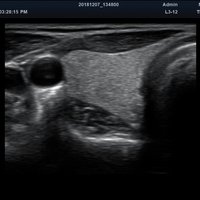

Das Alpinion minisono ist ein tragbares Hand-Ultraschallgerät, das eine sichere und schnelle Diagnostik u. a. in den Anwendungsbereichen Abdomen, MSK, Vaskulär, kleine Organe sowie Bauch und Brust bietet. An das minisono kann über USB-Kabel entweder eine Linear-Sonde oder eine Konvex-Sonde angeschlossen werden. Die komplette ultraschallspezifische Hardware ist in den Griffstücken integriert.

Dank seiner kleinen und kompakten Größe eignet sich das Ultraschallsystem für den Point of Care-Einsatz am Patientenbett, bei der Physiotherapie oder im OP. Das minisono kann darüber hinaus auch bei Hausbesuchen oder im Notarztwagen verwendet werden.

Das mobile Ultraschallgerät kann mithilfe eines USB-Kabels an das DT313Tmed-Medical Tablet, Microsoft Surface Pro Tablet oder ein anderes Windows-Tablet angeschlossen werden. Das vom Hersteller empfohlene Microsoft Surface 6 Pro-Tablet besitzt ein 12,3 Zoll PixelSense-Display. Mit seinem intuitiven Touch-Screen-Eingabefeld garantiert das minisono dem Benutzer einfachste Bedienung und liefert hochauflösende 2D-Bilder sowie Doppler-Informationen in kürzester Zeit.